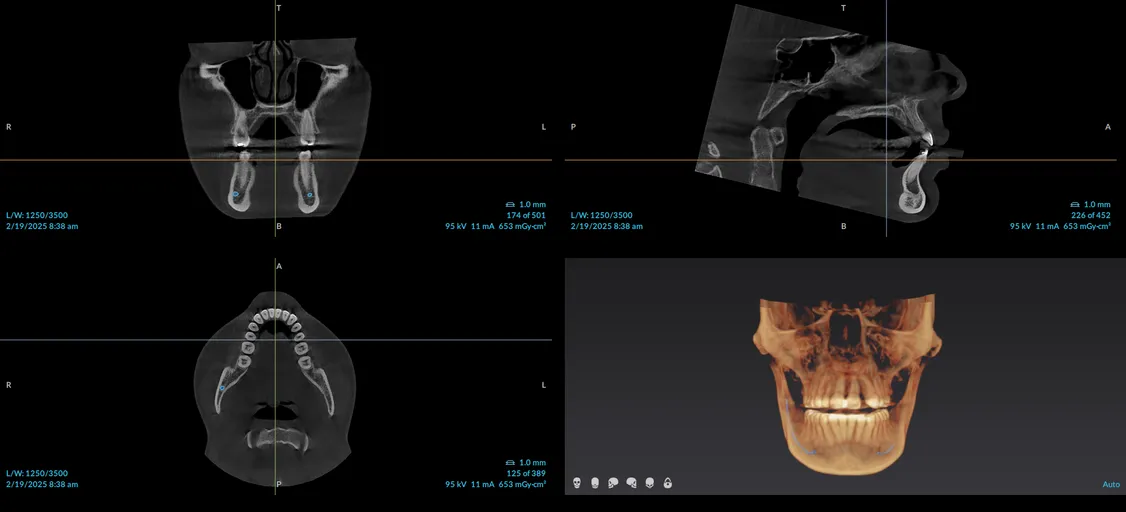

CT Scans and Cone Beam Imaging systems generate 3D, high definition x-rays within seconds. The panoramic images are remarkably clear, which helps with diagnosing and treating dental ailments. These scans allow us to quickly assess your dental needs and get you back out enjoying your life in less time than you might expect from traditional imaging equipment.  The health and safety of our patients is our highest priority, which is why we utilize a cone beam imaging system in our office. Unlike traditional x-ray systems, the Cone Beam system produces a very low dose of radiation, thus reducing unnecessary exposure. Some additional benefits of cone beam imaging include:

• Visualize anatomy that can not be diagnosed externally or from traditional x-rays

• Create better, more effective treatment plans

• Assess benefits and risk of treatment options

• Earlier detection of oral infections and tumors

CBCT image